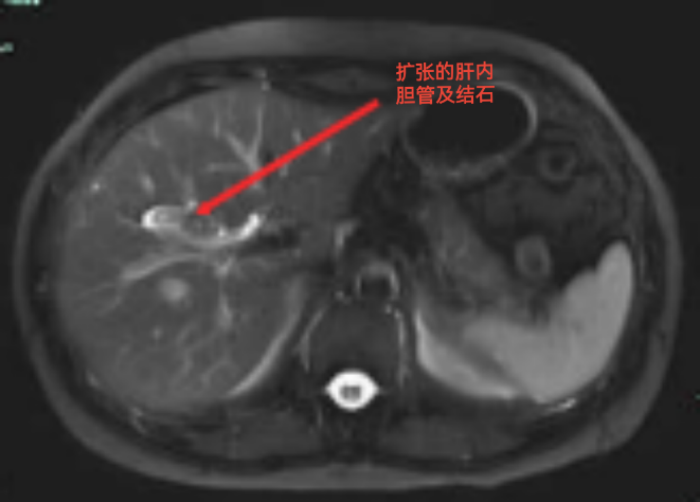

經(jīng)上腹部磁共振增強(qiáng)掃描,余女士被明確診斷為“膽囊結(jié)石;右肝內(nèi)膽管結(jié)石伴膽管擴(kuò)張;右肝小囊腫?!?